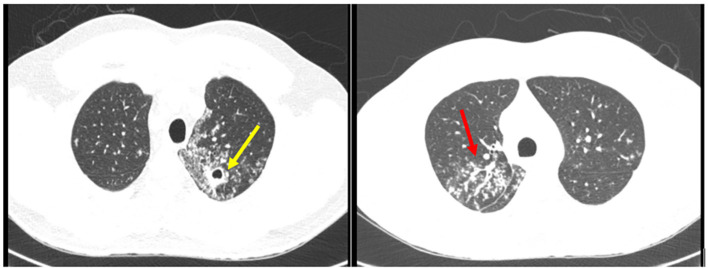

Psoas muscle abscess is an insidious disease, with varied clinical manifestations and a challenging diagnosis. This pathology has been more frequently identified due to the increased availability of high-quality radiological imaging, such as computed tomography. In Brazil, Mycobacterium tuberculosis is the most common secondary etiologic agent of psoas abscess. We report the case of a 28-year-old immunocompetent man diagnosed with disseminated tuberculosis, affecting the lungs, lumbar spine, and psoas muscle, leading to permanent locomotion sequelae. This case is very relevant for osteoarticular complaints, as low back pain and limping were the initial symptoms. Diagnosis was confirmed by ultrasound-guided percutaneous drainage of the psoas muscle abscess and detection of the M. tuberculosis complex via Xpert MTB/RIF. A 12-month treatment with antitubercular drugs was effective.